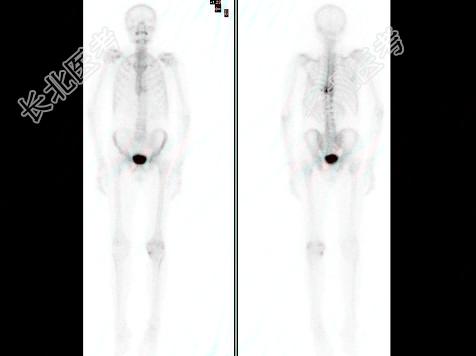

- 多项选择题男,68岁, 胸背痛3个月入院,行

Tcm-MDP全身骨显像、局部断层骨显像+X线图像融合如图, 可能的诊断是 ( )

A、胸9、10椎体良性压缩性骨折

B、大致正常的骨影像

C、胸9、10椎弓根受累,提示恶性病变

D、多发性骨髓瘤

E、胸9、10骨转移可能性大